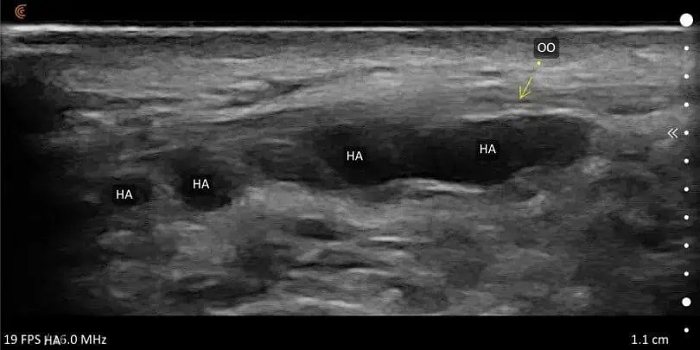

玻尿酸饅化的超音波影像

玻尿酸在超音波上算是最容易辨認的材質,看起來像:透明、水珠狀的低密度區域。